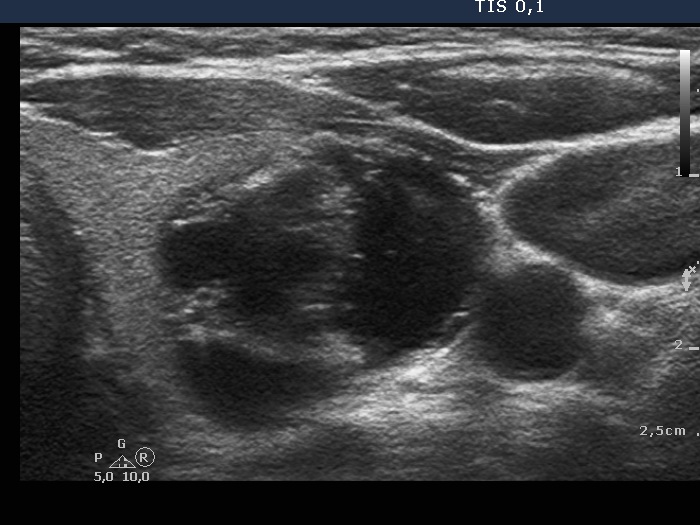

Study on 100 consecutive patients with thyroid nodule - case 042

Three years after the initial examination (ultrasonographic picture 4)

Left lobe, transverse scan - enlarged view. The echogenic figures here are back wall ones.